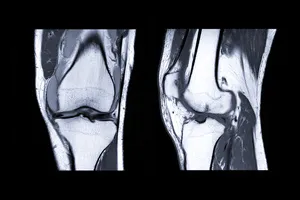

무릎 연골주사는 퇴행성 관절염이나 스포츠 손상 등으로 인해 손상된 무릎 연골을 보호하고, 통증을 완화하기 위해 사용되는 비수술적 치료 방법입니다.

주사액의 주성분은 히알루론산으로, 우리 몸의 관절액에도 존재하는 성분입니다. 히알루론산은 관절의 윤활 작용을 도와 부드러운 관절 운동을 가능하게 하고, 연골을 보호하는 역할을 합니다.